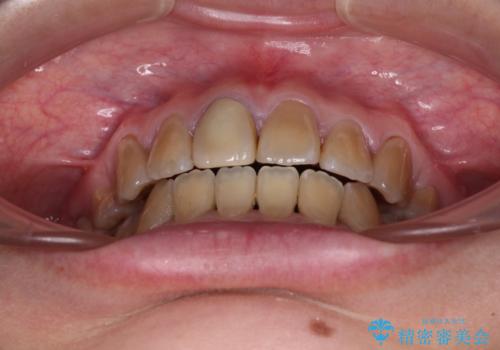

- 八重歯や前歯のデコボコを気にして来院された患者様です。

歯列が前方に傾斜しており、デコボコが強かったため、上下左右第一小臼歯4歯を抜去し、ワイヤー装置による矯正治療を行うこととしました。

上下の正中がずれていましたが、抜歯矯正であったので、極力正中位置を合わせるように治療を進めて行きました。

顎間ゴムの使用などにより、正中位置を改善することができました。